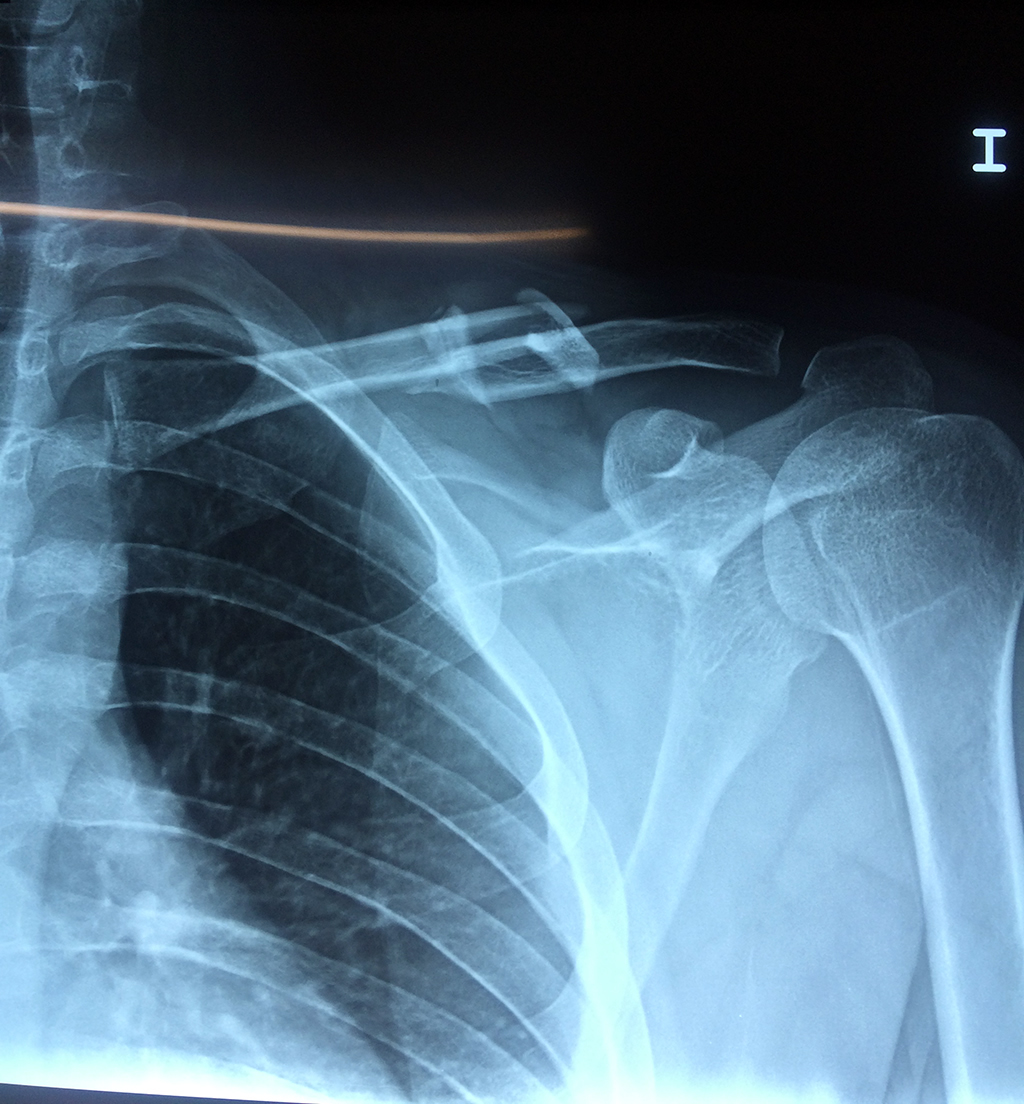

Cirugías de Calcaneo - Clavícula